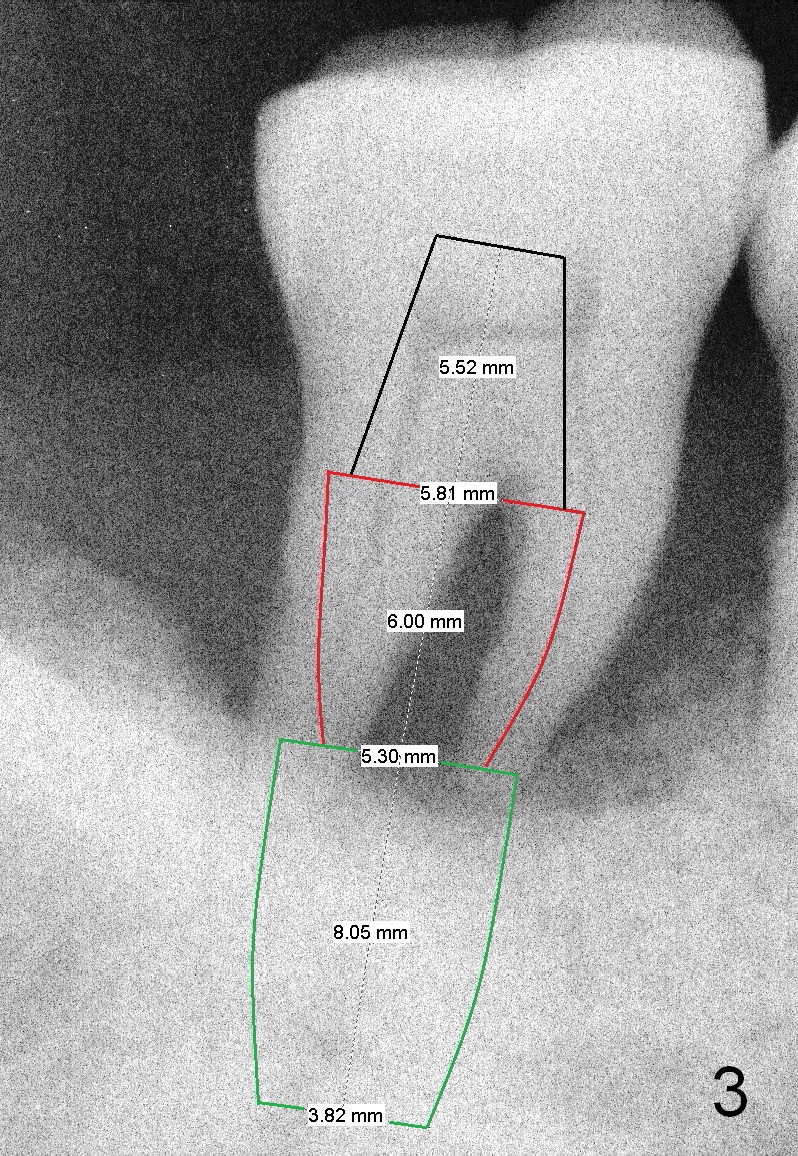

A 46-year-old lady has generalized moderate localized severe (Fig.1 (panorex) #31) chronic periodontitis. Surprisingly there is sufficient bone height (Fig.1 white dashed line: upper border of the Inferior Alveolar Canal). The gingiva is quite thick (Fig.2 (PA) arrowheads: gingival margin). In order to prevent thread exposure associated with immediate implant, a bone-level implant will be placed (Fig.3 5.3x8 mm; green lines) with a long abutment (5.8x5.5 mm (black lines) (6 mm cuff; red lines)). Initial osteotomy depth is between 14 and 17 mm. Insert a parallel pin and take the 1st intraop PA. Use reamers to enlarge osteotomy and collect autogenous bone. A drill with a stopper (5x8mm) will be used prior to placement of the implant mentioned above. Since the opposing is a removable partial denture, an immediate provisional at the site of #31 should be safe to be fabricated. Bone graft will be placed to cover the exposed implant surface. The remaining gap will be filled with collagen dressing and the provisional. A temporary abutment is the other option. The shoulder of the temporary abutment will be subgingival to long extent. Is the plan well executed?